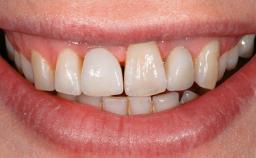

A 77-year-old male patient was referred for the management of frequent and repeated acrylic fracture of his existing mandibular fixed full-arch implant-supported metal/acrylic prosthesis. He also complained about softtissue soreness and the lack of retention and stability of his maxillary removable partial metal/acrylic prosthesis. Both prostheses had been delivered two years previously as part of his full-mouth rehabilitation (caries, tooth wear, tooth fracture). His medical history revealed high blood pressure, controlled with the use of antihypertensive medication.

Patient's Esthetic Expectations Low Medium High

Lip Line No exposure of papillae Exposure of papillae Full exposure of mucosa margin

Esthetic Risk Low